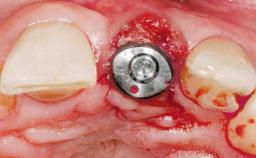

Early Placement of an Implant in a Maxillary Right Central Incisor Site

This 41-year-old female patient was referred to the clinic for the replacement of the right central incisor, since the tooth had developed a root fracture in the long axis that made extraction necessary. The healthy, non-smoking patient was first seen with the tooth still in place. A detailed Esthetic Risk Assessment was performed.The patient was worried about her dental esthetics and had high expectations for a successful treatment outcome from an esthetic point of view. The patient had a medium lip line that displayed parts of the gingiva in the anterior maxilla upon smile.

Bone Augmentation Horizontal|Simultaneous

Augmentation Materials Autogenous chips|Xenogenous|Membrane

Bone Volume Deficient horizontally, allowing simultaneous augumentation